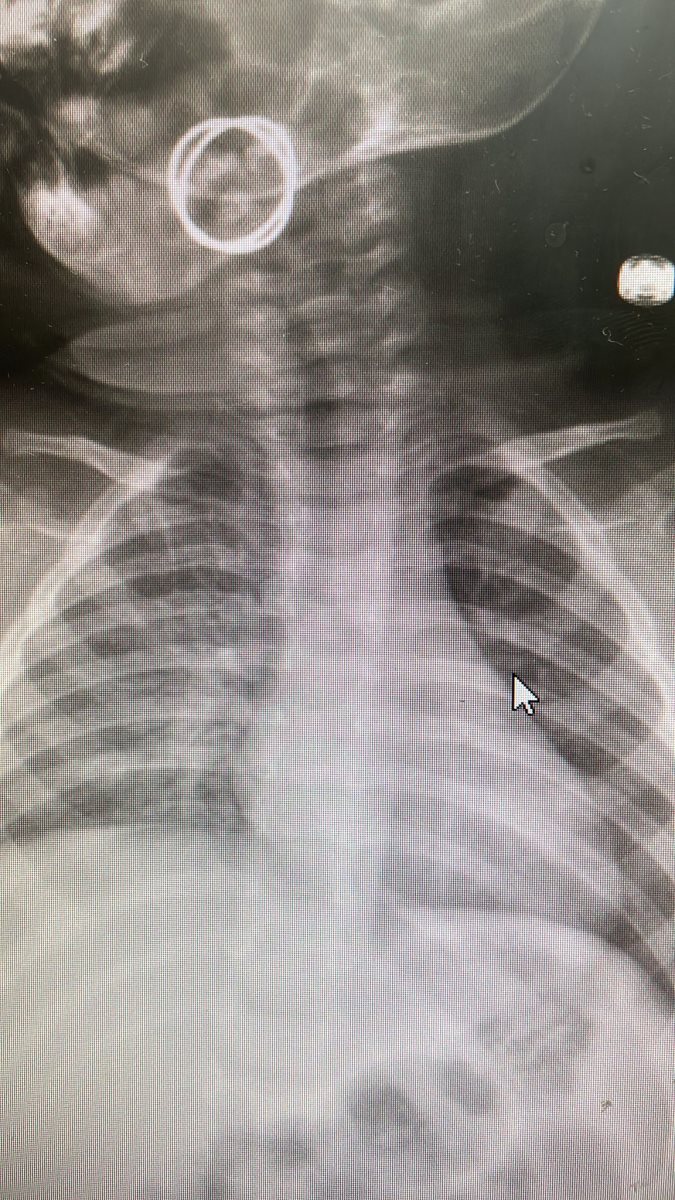

פעוט בן 9 חודשים הובהל לחדר המיון בסורוקה זאת לאחר שבלע טבעת. הטבעת הוצאה מגופו באמצעות פינצטה, כאשר מצבו מוגדר כעת כטוב

בחדר הלם במלר"ד בית חולים סבן לילדים בסורוקה הגיע פעוט בן 9 חודשים אשר לדברי אימו בלע טבעת. בבדיקה בחדר ההלם נצפה גוף זר בתוך הלוע והוצא באמצעות פינצטה על ידי ד"ר יותם אייליג, רופא במחלקה לאף אוזן גרון. לאחר השגחה בחדר המיון שוחרר הילד לביתו כשהוא במצב טוב.